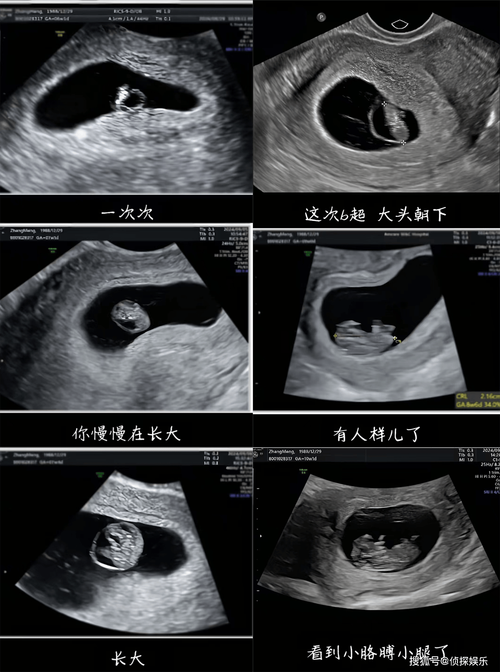

为什么会做这么多次B超?

虽然通常建议的B超次数在5-8次左右,但在某些情况下,医生可能会增加检查的频率,十几次的B超通常不是“常规操作”,而是出于以下一些特殊原因:

保留好检查报告,建立完整档案 将所有的B超单和产检报告整理好,按时间顺序排列,这能帮助您清晰地看到整个孕期的变化轨迹,也方便医生进行前后对比,做出更准确的判断。

(图片来源网络,侵删) -